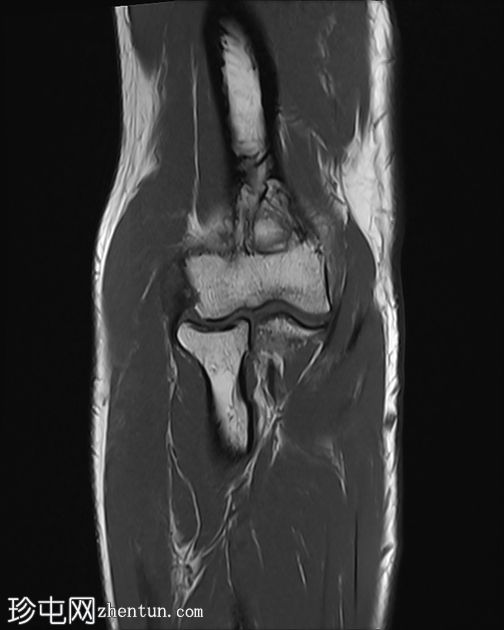

MRI

冠状位

T1加权像

肘关节伸肌总腱增厚,腱内可见高信号及部分撕裂。伴周围软组织水肿。

本病例展现了网球肘的典型

影像

学特征。